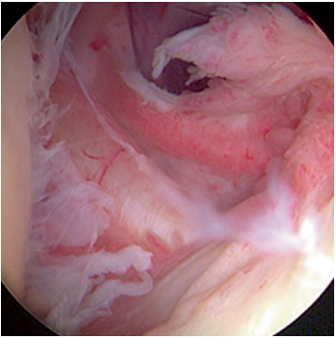

Die Bezeichnung adhäsive Kapsulitis, die 1945 vom amerikanischen Chirurg Dr. Neviaser gewählt wurde, ist nach den heutigen Erkenntnissen der Erkrankung ziemlich irreführend. Frozen Shoulder betrifft in erster Linie die Schultergelenkkapsel, welche sich durch Entzündungsprozesse verdickt und dadurch die Beweglichkeit einschränkt. Sie ist nicht verklebt oder angewachsen.

Normale Schulter Entzündete Kapsel bei Frozen Shoulder